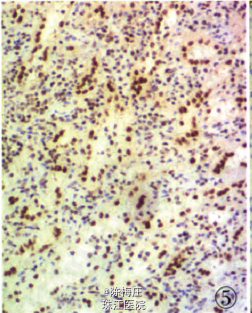

初步诊断:子宫肌瘤,子宫腺肌病,盆腔多发肿物性质待查。 确定诊断:盆腔腹膜脾组织植入。 完善相关检查,行全子宫切除术。病理检查:眼观:全切子宫1个,13 cm×8 cm×5.5 cm大小,子宫做多个切面,在肌层内查见2个大小不等灰白色肌瘤,肌瘤面积O.3 em×0.2 cm—l cm×0.66cm,肌瘤切面质韧,灰白色,呈编织状,边界清;内膜光滑,厚0.2—0.3 em,肌层厚2.5—3.5 cm,部分呈海绵状,子宫颈光滑,切面质韧,质地较细。盆腔内不规则肿物1个,灰红色,表面结节状,11cm×7.5 cm×3.5 cm大小,做多个切面,切面见多个结节,结节面积:0.4cm×0.3 cm~4.3 cm×2.5 cm,结节切面质脆,灰红色,质地细,结节边界清。另送圆形结节5个,直径1~3 cm不等,切面性质同盆腔较大肿物,均有包膜(图1)。镜检:患者子宫检查为子宫肌瘤,子宫腺肌病,病变无特殊性。盆腔多个肿物病变性质基本一致,为扩张血窦样组织,窦腔内充满红细胞,似脾红髓淤血(图2),在血窦样组织间有大小不等、发育良莠不齐的白髓样结节,结节较大者有小中央动脉(图3),结节较小者中央动脉不明显,内皮细胞无异型性,细胞分化均无异性,无病理性分裂象。可见玻璃变性纤维结缔组织似脾小梁样结构(图4)。免疫表型:血窦样内皮细胞nFli-1强阳性(图5),CD31弱阳性;CD34肿物小血管强阳性而血窦内皮细胞阴性(图6),CR和SMA均阴性;Ki-67增殖指数为5%。